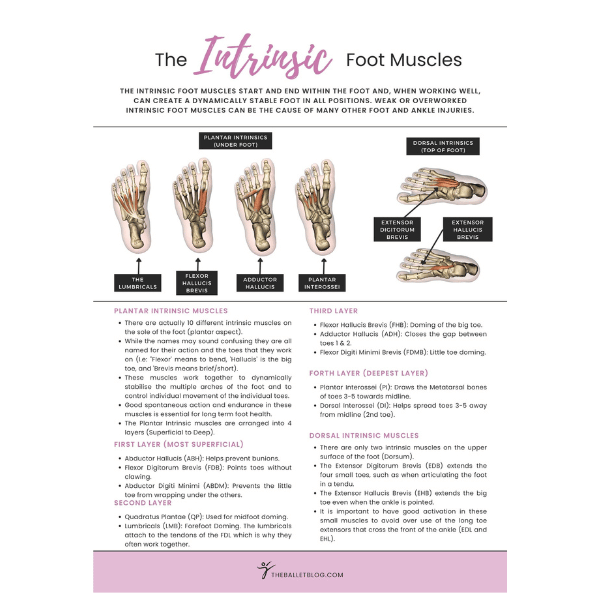

Dancing en pointe is a magnificent art form that has completely defined ballet as a practice. It poses many physical challenges for aspiring dancers with many aspects of the body's function being utilised. Over the years, we have been constantly refining our knowledge of pointe work from a physiotherapist's perspective to give you the most up-to-date ideas from the world of dance medicine. We aim to answer your questions and to help you fast-track your progression en pointe.